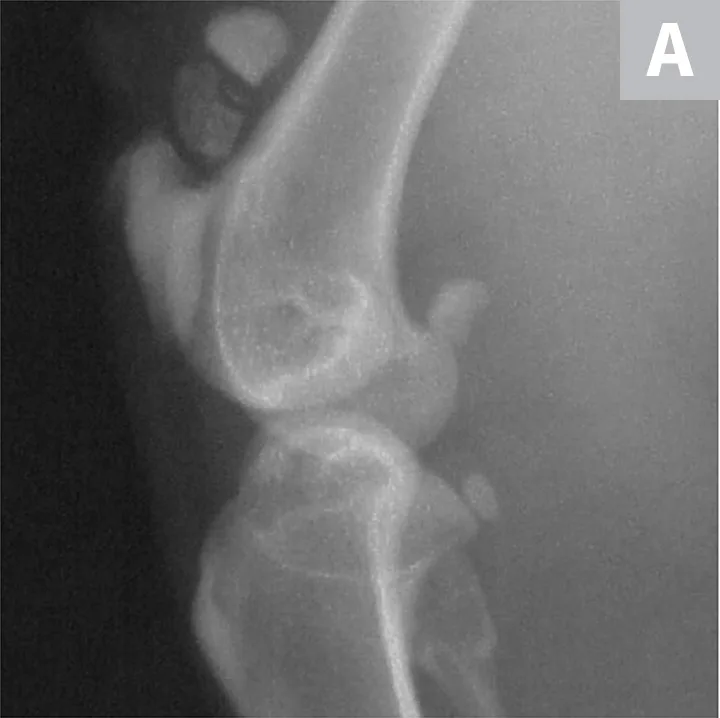

The patient received buprenorphine (15 µg/kg IV) for analgesia, followed by an induction with alfaxalone (0.5 mg/kg IV) and general anesthesia with isoflurane to facilitate dental and orthopedic radiography. Dental radiographs revealed persistent deciduous teeth and impacted permanent teeth. Lateral and craniocaudal pelvic limb radiographs revealed a displaced left patellar fracture and a nondisplaced right patellar fracture (Figure 2).

Lateral radiographs of the left (A) and right (B) stifles show a complete, displaced left patellar fracture and a nondisplaced right patellar fracture, respectively.